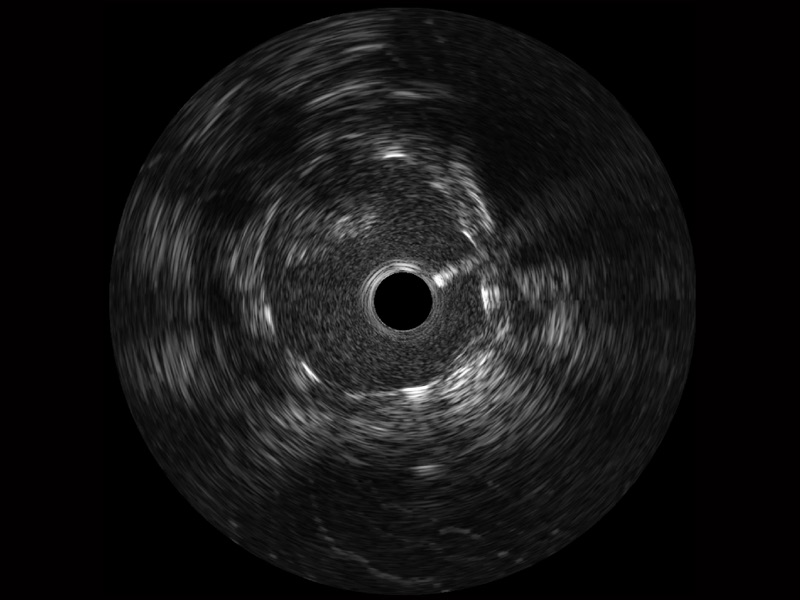

milan米兰宽频IVUS图像

传统IVUS图像

对比传统IVUS导管成像,milan米兰宽频IVUS图像的近场支架梁显影更细腻,远场中膜外血管仍清晰可辨,兼顾远中近,兼顾分辨力与穿透深度